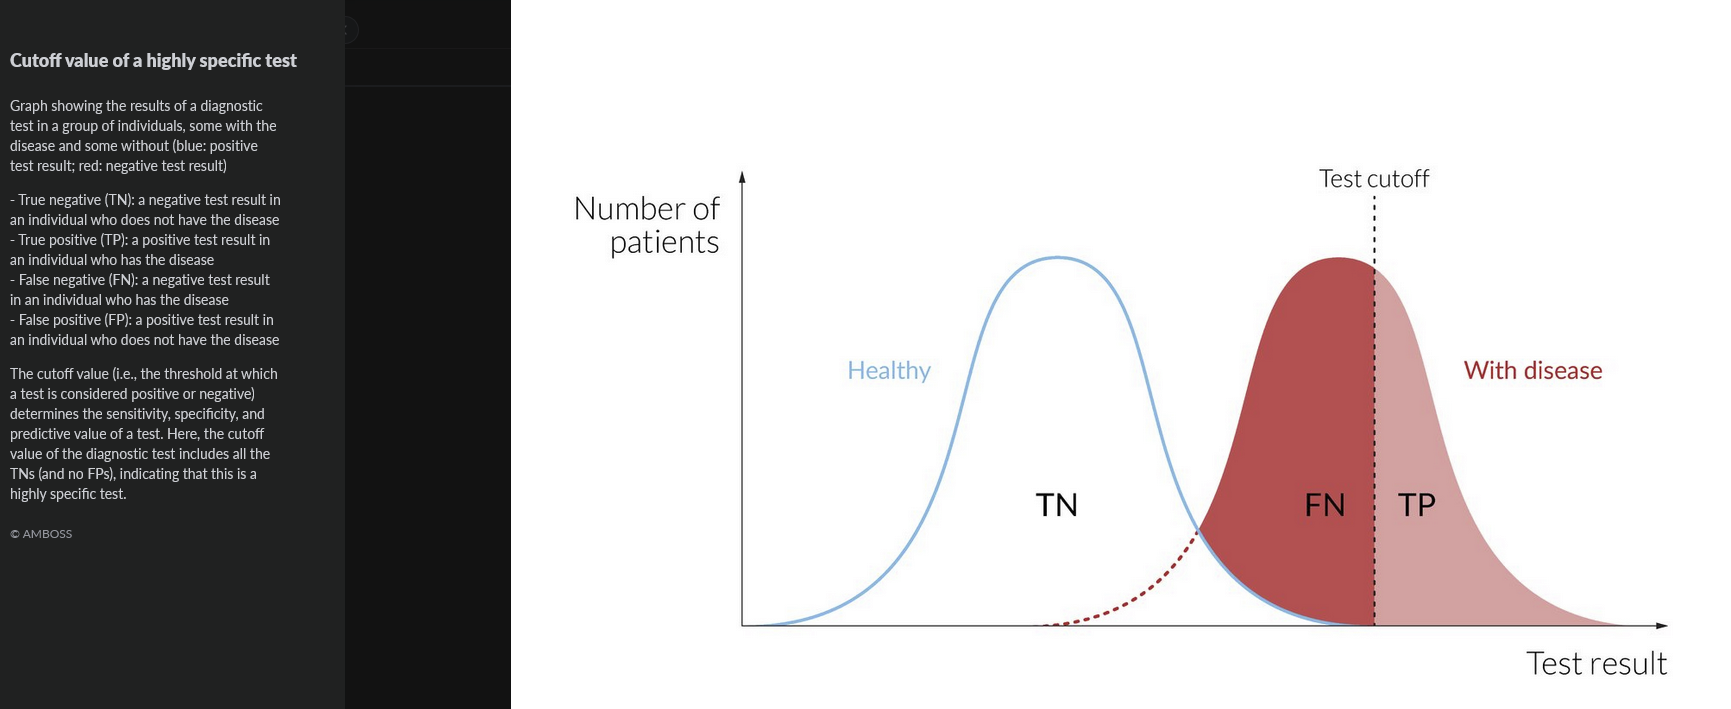

sensitivity =

proportion of individuals with disease for which the test was positive

TP/(TP+FN)

rules OUT disease, best for screening

specificity =

proportion of individuals without the disease with a negative test

TN/(TV+FP)

CONFIRMS disease, best used after a high-sensitivity screening test

1 - sensitivity =

false negative rate

1 - specificity =

false positive rate